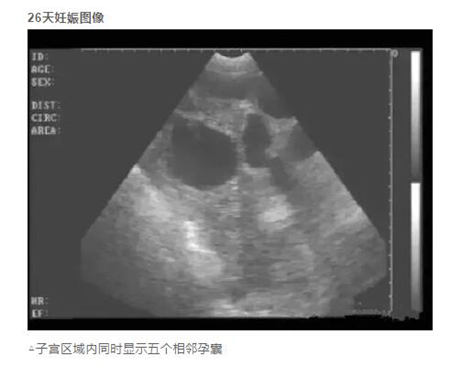

20天孕期左右的母猪,即可进行B超测孕,但由于羊水太少,图像不好判断,准确度也会因检测人员经验因素有所影响,容易造成误判,而且检查时间长,耗费人力。